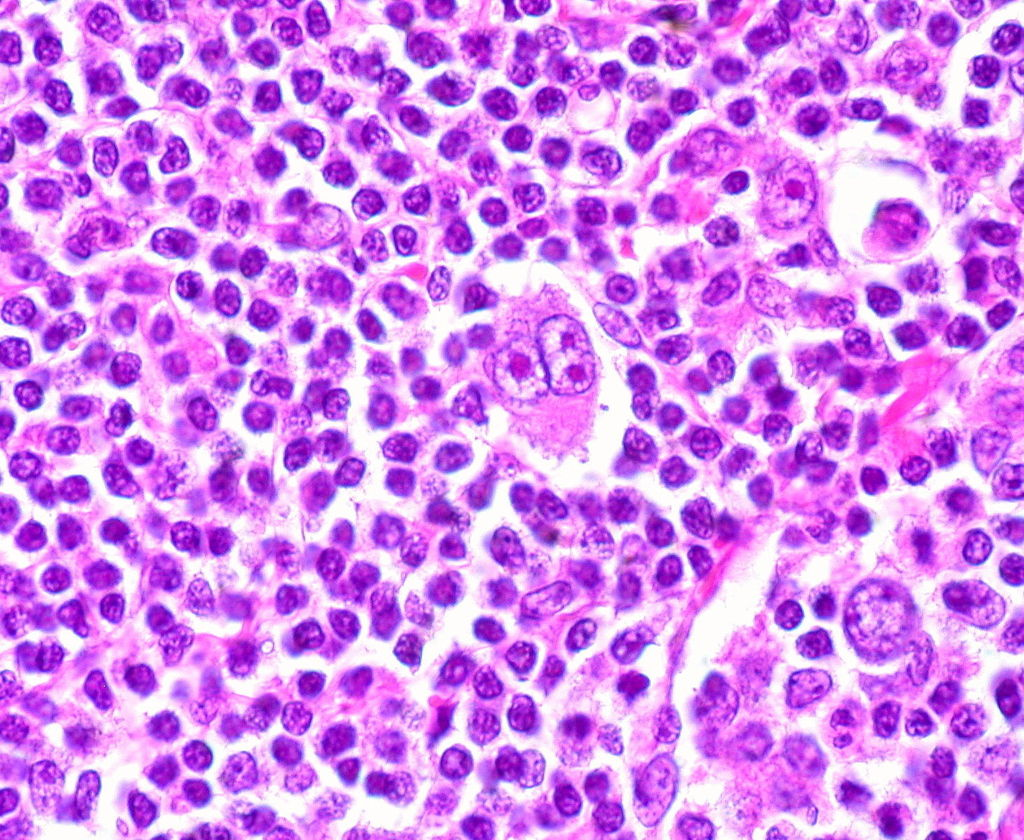

36.下列何種疾病的病理組織最常看到Reed-Sternberg cells?

(A)Hodgkin lymphoma